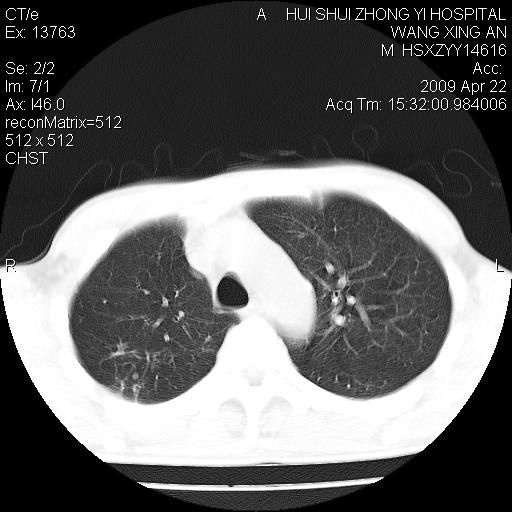

标题: CT19534:患者男、46岁咳嗽、胸痛半月。 [打印本页]

标题: CT19534:患者男、46岁咳嗽、胸痛半月。

1、右下肺中央型肺癌并右肺转移,右肺下叶不张。(右肺有结节影)。

2、右中上肺陈旧性肺结核(因为大多为纤维灶)。

3、右侧胸腔积液。

1、右下肺中央型肺癌并右肺转移,右肺下叶不张。(肿块围绕右肺下叶支气管生长,致管腔闭塞右肺下叶不张;右肺有结节影)。

2、右侧胸腔积液。

3、右中上肺陈旧性肺结核(右肺见纤维化病灶及点状钙化)。

1。右下肺中央型肺癌并肺转移,右肺下叶不张。(两肺都有结节影)。

1)右肺中间段支气管癌并右肺下叶肺不张。2)右肺上叶、两肺下叶背段感染性病变。3)右侧少量胸腔积液。